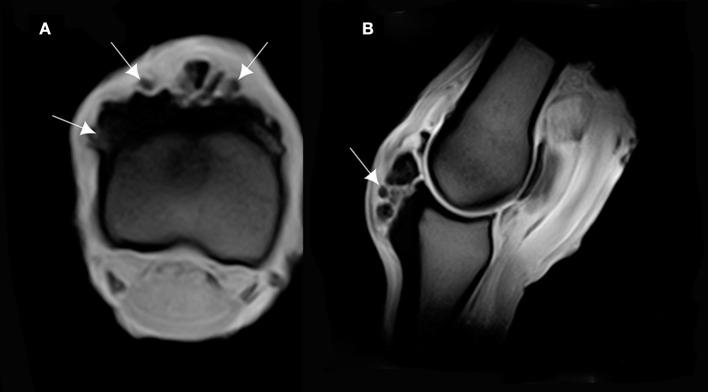

This study aimed at describing anatomo-histopathological and imaging features, using computed tomography and magnetic resonance imaging on six forelimbs of Tbourida horses, that presented a particular bone exostosis on the dorsal and proximal part of the first phalanx, diagnosed by X-ray. Gross anatomy of the bone exostosis revealed an irregular surface with poly-lobulated tissue masses showing a cauliflower shape. The diameter/depth varied from 0.5 to 5.1 cm with a mean of 3.9 ± 0.9 cm. The capsule of the metacarpophalangeal joint was hypertrophic and showed many invaginations in the inner part, in contact with the bone exostosis. Computed tomography revealed cortical and medullary continuity of the bone exostosis, with the underlying bone, and remodeling of the cortical surface of the dorsal and proximal part of the first phalanx. Magnetic resonance imaging showed an increased signal intensity of the bone exostosis on the T1- and T2-weighted gradient fast echo. Histological examination of the bone exostosis revealed a cap of hyaline cartilage, including large foci of endochondral ossification with a base of cancellous bone surrounding marrow spaces, which confirmed the diagnosis of osteochondroma. The capsule of the metacarpophalangeal joint showed a large amount of recently formed connective tissue fibers in its inner part, interspersed with mature connective tissue. The hyperextension of the metacarpophalangeal joint during a Tbourida show, which occurs on a hard ground surface, and the use of hobbles in horse stabling are most likely responsible for the outgrowth of an osteochondroma of different shapes and sizes, and fracture complications in some cases.

本研究旨在描述6匹图里达马前肢的解剖组织病理学和影像学特征,这些马的第一指骨背侧和近端出现了一种特殊的骨外生骨疣,通过X线诊断。骨外生骨疣的大体解剖显示其表面不规则,有多个分叶状组织块,呈菜花状。直径/深度在0.5至5.1厘米之间,平均为3.9±0.9厘米。掌指关节的关节囊肥厚,内部有许多内陷,与骨外生骨疣接触。计算机断层扫描显示骨外生骨疣与下方骨骼的皮质和髓质连续,第一指骨背侧和近端的皮质表面有重塑。磁共振成像显示在T1加权和T2加权梯度快速回波上骨外生骨疣的信号强度增加。骨外生骨疣的组织学检查显示有一层透明软骨帽,包括大量软骨内成骨灶,其底部为围绕骨髓腔的松质骨,这证实了骨软骨瘤的诊断。掌指关节的关节囊内部有大量新形成的结缔组织纤维,夹杂着成熟的结缔组织。图里达马表演期间在坚硬地面上发生的掌指关节过度伸展以及马厩中使用缰绳极有可能导致不同形状和大小的骨软骨瘤长出,在某些情况下还会引发骨折并发症。